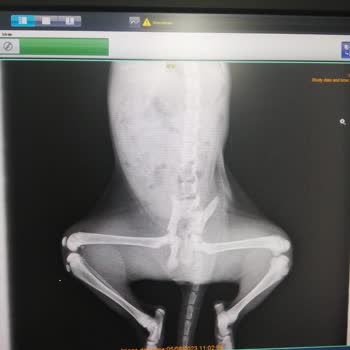

17 Kasım 2025 günü saat yaklaşık 16.25'te, sokakta baktığım ve sorumluluğunu üstlendiğim, bacağı kırık olan bir kediyi dikili Belediyesi veteriner işleri müdürlüğü’ne bağlı, Gazipaşa 35980 civarında bulunan belediye veteriner kliniğine teslim ettim. Kediyi teslim ettikten sonra sağlık durumu ve yap...